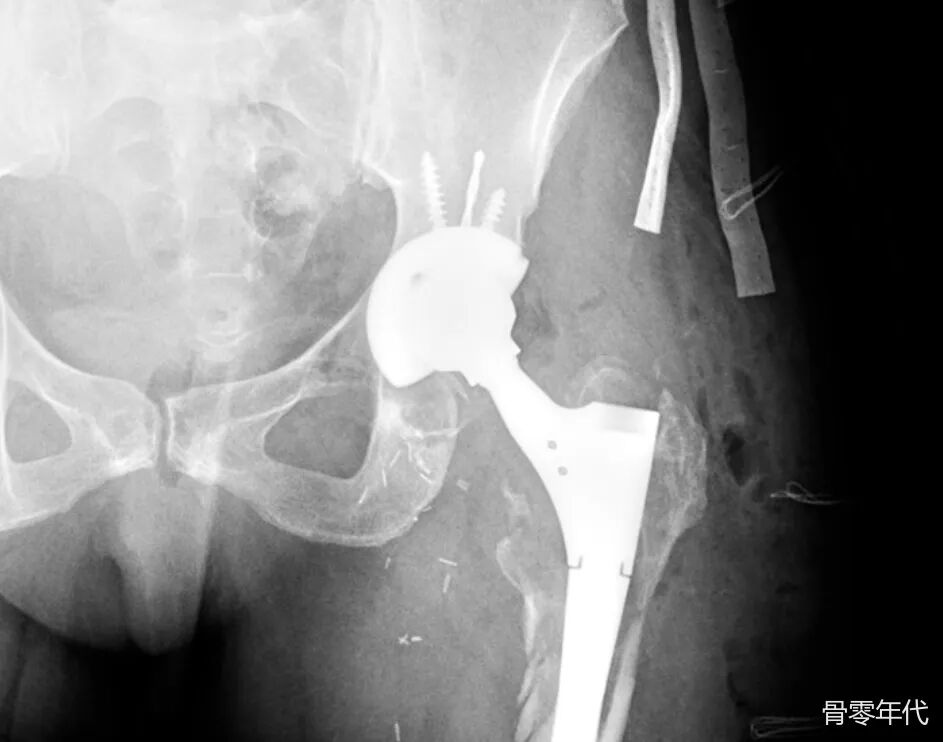

左侧骨盆X光片,翻修髋关节假体。